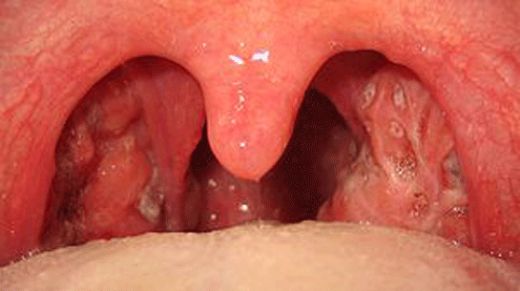

Kronik bademcik iltihabının belirtilerini yaşayan biri olarak, sık sık boğaz ağrısı ve kötü nefes kokusu yaşıyorum. Büyümüş ve deforme olmuş bademciklerim de var. Bu belirtilerle sık sık karşılaşan biri olarak, boğaz enfeksiyonlarımın kronik bademcik iltihabından kaynaklanıyor olabileceğini düşünüyorum. Tedavi için hangi adımları atmam gerek?

Kronik bademcik iltihabı yaşadığınız belirtilerden anlaşılıyor. Bu durumda tedavi için birkaç adım atabilirsiniz. Öncelikle bir kulak burun boğaz (KBB) uzmanına başvurarak detaylı bir muayene olmalısınız. Doktorunuz, bademciklerinizi inceleyerek gerekirse kan testleri ve boğaz kültürü gibi ek tetkikler yapabilir.